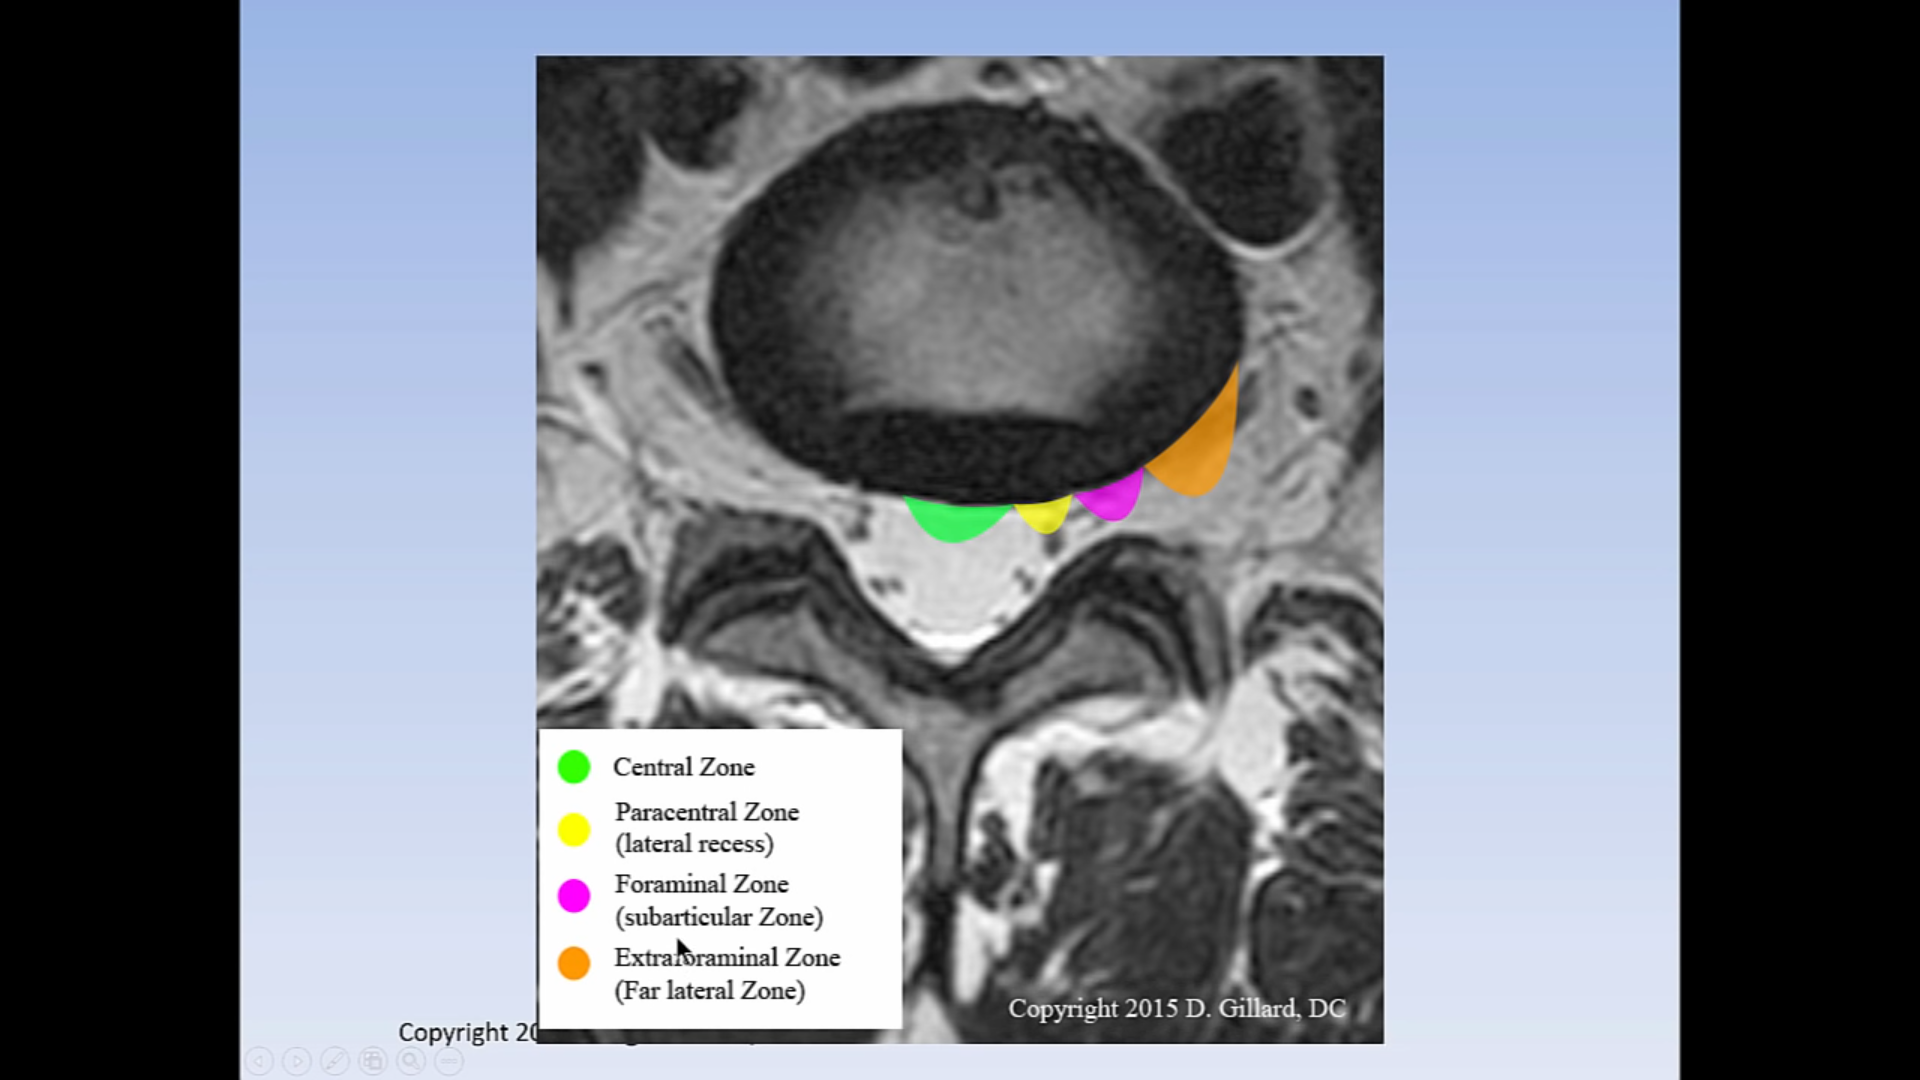

Лечението на дискова херния може да бъде консервативно или хирургично. В консервативното лечение се използват нестероидни противовъзпалителни лекарства, аналгетици, физиотерапия, балнеолечение, ЛФК и други. Хирургичното лечение се налага в случаи на тежки увреждания или когато консервативните методи не доведат до подобрение. Алтернативните лечебни методи за дискова херния включват остеопатия, боуен терапия, хомеопатия, озонна нуклеолиза и други алтернативни терапии, които се различават от традиционните медицински подходи. Основните методи за лечение на дискова херния включват първична терапия с противовъзпалителни лекарства, почивка, подходящи упражнения, физиотерапия, кинезитерапия, ергономични столове и правилна стойка при седене. В някои случаи може да са необходими хирургични интервенции. Различните лечебни методи за дискова херния включват физиотерапия, масажи, балнеолечение и упражнения. Тези методи могат да се използват преди и след операция. Освен това е важно да се консултират с неврохирург и ортопед за персонализиран подход към лечението.